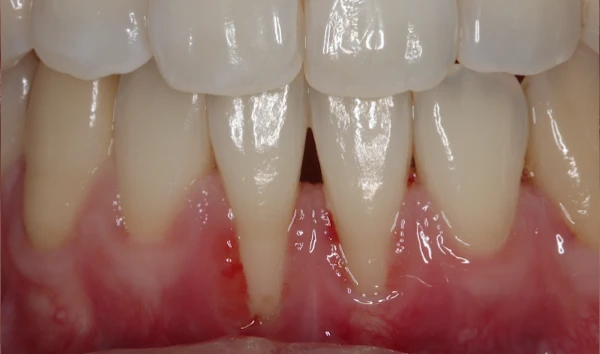

審美歯周病治療

見た目も美しく

歯周病治療を行うと歯茎が下がったとよく聞きます。残念ながら、炎症が長期に渡り存在していた歯茎や、重度歯周病では、治療を行うことにより歯茎が下がり炎症が除去されると歯茎が下がってしましやすいです。そういった場合、セラミックス治療を行うことで審美的に改善を図ることがあります。

また、歯周病はないのに、歯茎が下がってしまうことによる審美性が損なわれてしまう病気があります。そのような場合、歯茎の移植などを行うことにより、歯を削ることなく審美性を改善させることができます。 -